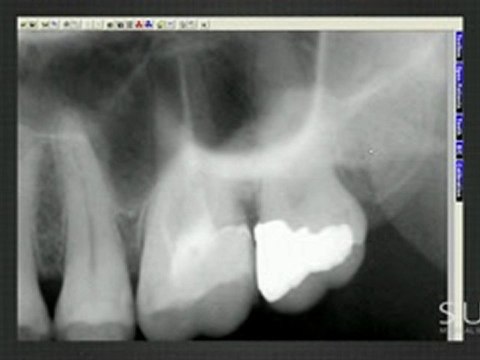

Intraoral, Case, Studies, Imaged, with, Suni, Sensors, Chapter